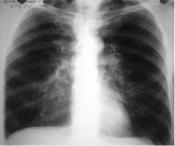

Рентгенография органов грудной клетки: Первичное рентгено-

логическое исследование проводят для исключения других заболеваний (рака легких, туберкулеза и др.), сопровождаемых аналогичными с ХОБЛ клиническими симптомами. При установленном диагнозе ХОБЛ рентгенография органов грудной клетки необходима в период обострения заболевания для исключения пневмонии, спонтанного пневмоторакса, плеврального выпота и пр.

Определяется усиление или сетчатая деформация легочного рисунка, а также признаки эмфиземы легких: низкое стояние купола диафрагмы и ограничение ее движений, повышение прозрачности легочных полей.